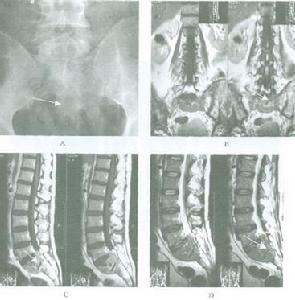

1.X 線檢查 胸部X 線檢查為重要的常規檢查。從目前資料分析縱隔淋巴瘤沒有明確的診斷性放射學特徵。但或多或少可以輔助診斷。霍奇金淋巴瘤以上縱隔和肺門淋巴結對稱性融合呈波浪狀凸入肺野、淋巴結間界限不清為典型改變,累及氣管分叉和肺門淋巴結較氣管旁淋巴結為多。侵犯前縱隔和胸骨後淋巴結是霍奇金淋巴瘤又一特徵性X 線表現。 霍奇金淋巴瘤總是先有縱隔和肺門淋巴結病變,然後出現肺內病變。肺內特徵性表現為呈光芒放射狀的索條影,可能與肺內淋巴管向肺門引流受阻有關。霍奇金淋巴瘤可出現胸腔積液,但胸腔積液作為惟一的X 線表現罕見。如 腫瘤巨大會造成周圍器官及組織壓迫,導致上腔靜脈梗阻,氣管移位,肺不張,並侵入胸壁、胸骨和(或)胸壁同時受侵犯。可以是腫瘤直接侵犯也可以是乳內淋巴結腫大侵犯所致,為重要放射學表現。腫瘤經乳內淋巴鏈轉移可侵犯肋間淋巴結,並在脊柱旁形成腫塊。同時 胸壁淋巴結轉移或心包受累可導致一側心包旁淋巴結,膈肌淋巴結和(或)膈肌受侵犯。上述表現雖不是霍奇金淋巴瘤特異性表現,但對診斷及制定治療方案很有意義。

2.CT 掃描 有學者複習診斷明確的霍奇金淋巴瘤CT 片後發現70%的病人有胸部侵犯,一般腫塊邊緣不規則密度不均,有時腫瘤包繞血管,並向四周縱隔浸潤。它向外侵犯方式為向心性表現,即從前縱隔或旁縱隔的淋巴結向四周淋巴結侵犯,然後到肺門區隆突下,橫膈組和乳內淋巴結,極少累及後縱隔淋巴結。肺轉移為後繼表現並可侵犯胸膜、心包和胸壁,表現為 胸腔積液,心包積液。胸壁受侵常為前縱隔和乳內淋巴結病變向胸壁蔓延,沒有胸內淋巴結受侵而腋淋巴結受侵者少見。